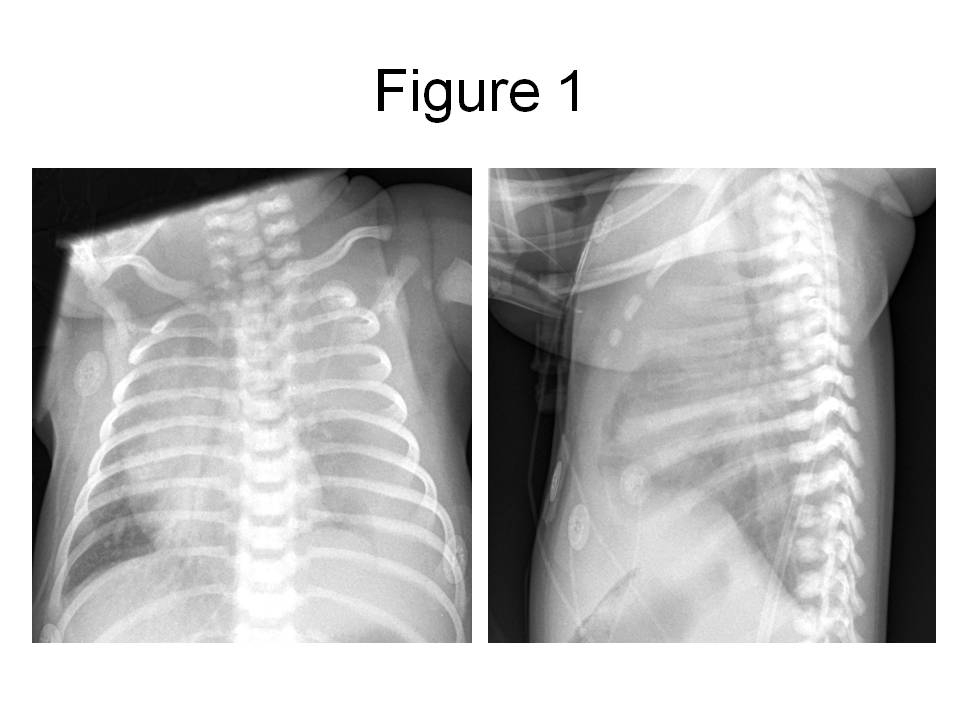

Figure 1. PA and lateral chest radiograph obtained in the emergency room, revealing a large left pleural effusion with displacement of the mediastinal structures into the right chest.